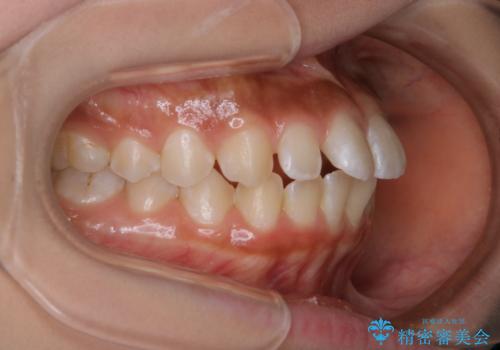

- 上の歯がすきっ歯なのと、歯が出ている気がするとご相談にいらした方です。

奥歯の噛み合わせに大きな問題がなく、患者様のご希望もあったため、前歯部メインで治療するインビザラインLiteで治療を行いました。

横顔のシルエットが改善し、口元もスッキリとなりました。